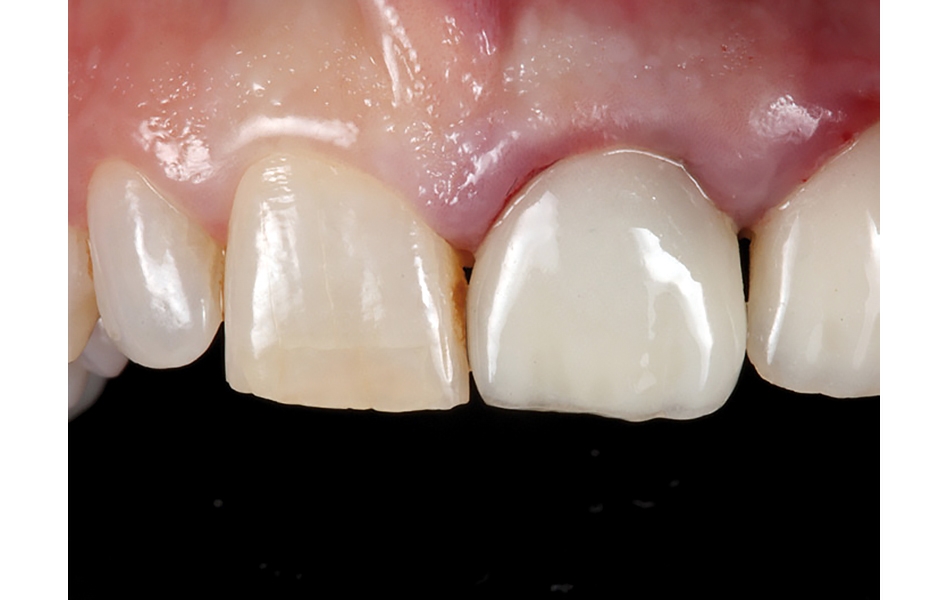

- Obr: 14: Umisťování provizorních náhrad z PMMA.

- Obr. 15: Dobré hojení měkkých tkání 4 dny po operaci.

- Obr. 16: Úprava provizorních korunek podle utvářejícího se emergence profilu 6 týdnů po operaci.